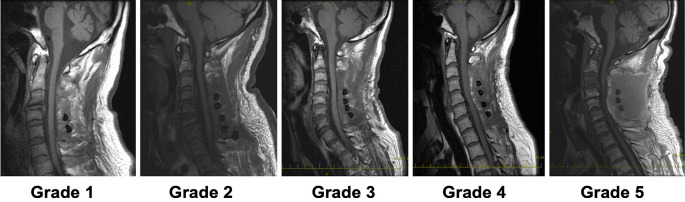

Methods: A total of 153 patients, consisting of 85 men and 68 women, were included in this study. Their mean age was 65.5 years. They were divided into two groups: Groups A and B. Group A (139 patients) did not receive preoperative antiplatelet agents, and Group B (14 patients) resumed antiplatelet agents from 7 or 14 days presurgery to 3 days postsurgery. Our analysis encompassed demographic data before surgery, postoperative magnetic resonance image-based assessment of radiological epidural hematoma (EH), and complications such as symptomatic hematoma, blood transfusion, stroke, and venous thromboembolism after surgery.